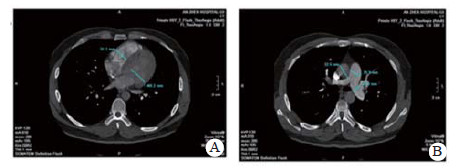

实验室检查结果:动脉血气分析pH 7.458, PaO2 60.5 mmHg, PaCO2 26.7 mmHg, SpO2 92.0%;D-二聚体2 655 ng/mL; BNP 163.00 pg/mL; 血常规WBC 5.91 ×1012/L, NE 73.8%, HGB 138.0 g/L, PLT 286 g/L; 同型半胱氨酸(HCY)14.0 μmol/L (正常值:6~14 μmol/L); 纤维蛋白原定量(FBG) 0.520 g/L(正常值:2.000~4.000 g/L), 纤溶酶原活性39.0%(73.0%~127.0%), 纤溶酶原抑制物-1(PAI-1)6.898 ng/mL(正常均数4.207 ng/mL), 组织纤溶酶原激活物(t-PA) 5.135 μg/L(正常均数2.375 μg/L); 血浆抗凝血酶Ⅲ(AT-Ⅲ:A)、血浆蛋白C活性(PC:a)、血浆蛋白S活性(PS:a)以及狼疮抗凝剂(Lupus anticoagulant, LA)水平在正常范围内。行经胸壁超声心动图检查提示右心扩大(因肺动脉瓣及三尖瓣反流极少, 无法准确估测肺动脉压力), 肺动脉增强CT(pulmonary artery computed tomography angiography, CTPA)提示右室扩大、两肺动脉主干及分支可见多发充盈缺损(图 2)。下肢静脉多普勒超声提示右侧腘静脉急性深静脉血栓形成及右侧股浅静脉血栓形成, 左侧髂静脉及左下肢深静脉未见明显异常。诊断为急性PE(高危组)、KTS。评估后给予重组组织型纤溶酶原激活物(r-tPA)50 mg 2 h内静脉泵入溶栓治疗, 溶栓过程中(r-tPA使用至35 mg时)患者出现咯血约200 mL, 遂被迫停止溶栓治疗, 监测活化凝血时间(accelerated clotting time, ACT)降至200s时给予普通肝素持续泵入并维持ACT于180~220 s, 肝素抗凝治疗48 h后改为低分子肝素(low molecular weight heparin, LMWH)联合华法林治疗, 期间未再发生咯血症状。入院第4天完善肺通气/灌注显像检查, 并提示:左肺下叶, 右肺中叶内段(亚段)、中叶外段、下叶前基底段、外基底段、后基底段血流灌注可见放射性分布稀疏缺损区, 双肺多发PE(累及8个肺段及1个亚肺段), 肺血流灌注受损范围占双肺容积的51%;入院10 d后复查CTPA, 结果显示两肺动脉主干腔内充盈缺损完全消失(图 3)。住院治疗15 d患者好转出院, 院外口服华法林抗凝治疗, 定期监测国际标准化比值(INR), 且维持于PE治疗范围2~3之间。抗凝治疗1年后进行肺通气/灌注显像复查, 提示右肺下叶前基底段、外基底段血流灌注改善, 左肺下叶, 右肺中叶内侧(亚段)、中叶外段、下叶后基底段血流灌注恢复正常。随访3年以来, 患者院外规律服用华法林抗凝治疗, 定期监测INR, 定期复查超声心动图及肺通气/灌注显像检查, 出院3个月超声心动图检查肺动脉压力正常、三尖瓣反流消失; 出院12个月及33个月复查肺通气/灌注未见新发的血流灌注稀疏缺损区, 出院33个月复查双髂双下肢静脉超声未见明显阻塞, 随访期间未出现出血或其他不良事件, 出院1个月后恢复工作至今, 一般状况良好。

| 图 2 患者CTPA(溶栓前):房室瓣水平显示右室明显扩张(A); 主肺动脉水平显示肺动脉增宽(B) |